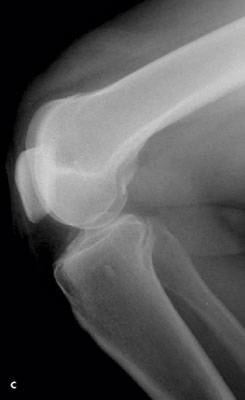

Knee pain following a soccer injury: The frontal radiograph reveals that the patella is dislocated laterally (A). This is confirmed on the sunrise radiograph (B). A lateral radiograph shows the malalignment of the patella with the distal femur (C). Most important, it also shows no fracture. Lateral dislocation of the patella is diagnosed.